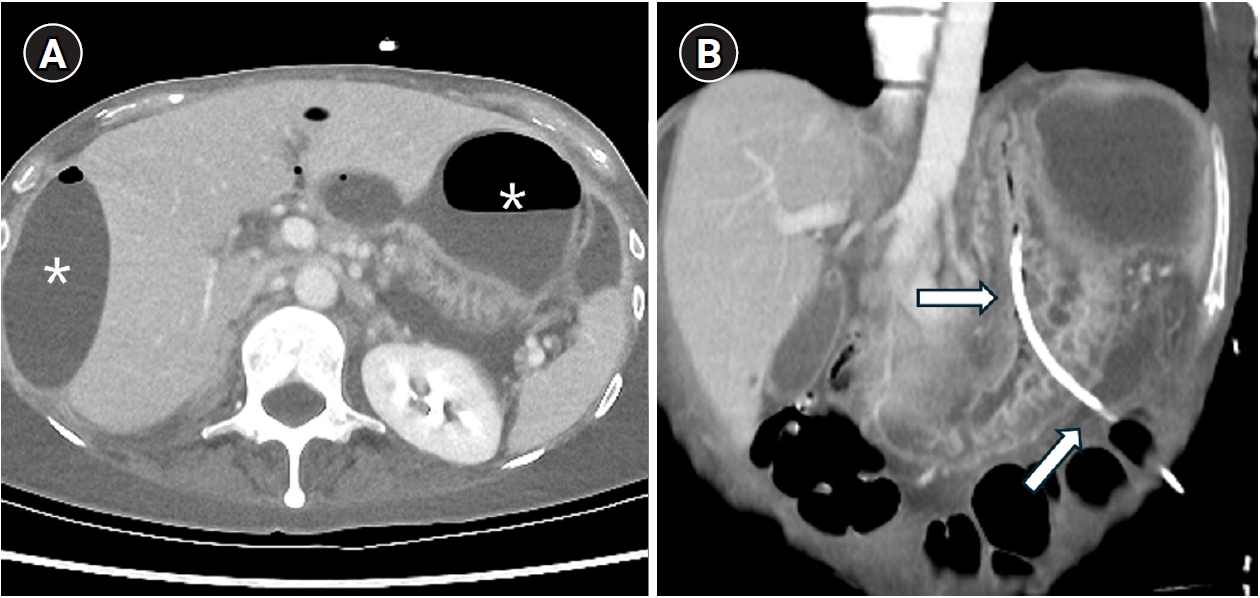

The cause of malposition was not clear, however, it may have been related to inadvertent advancement of the micropuncture needle or misinterpretation of ultrasonographic findings between the gas-filled stomach and the abscess. A wide space between the stomach and peritoneal wall, along with malnutrition due to prolonged fasting, may hinder normal tract maturation. In addition, instability caused by peristalsis and the lack of an anchoring system–unlike feeding gastrostomy–may further delay tract formation, necessitating safe closure of the perforation. After multidisciplinary discussion, safe retrieval of the PCD catheter was planned using a SMVCD instead of surgical treatment, as the patient had severe radiation-associated fibrosis from prior oncologic treatment. The catheter was exchanged over a 0.035-inch guidewire, and the SMVCD was advanced along the wire (

Fig. 2A). The foot was deployed and slightly retracted to achieve secure attachment under fluoroscopic guidance (

Fig. 2B). The needles pierced through the gastric wall by pushing the plunger and were then retracted (

Fig. 2C), and the puncture site was cinched using the suture trimmer (

Fig. 2D).

Fig. 2.Closing procedure. (A) An additional catheter was placed for perigastric fluid drainage (arrow). The misplaced drainage catheter was exchanged over 0.035-inch guidewire, and a suture-mediated vascular closing device was advanced along the guidewire (arrowheads). (B) The device foot was deployed and slightly retracted to create tenting of the gastric wall (arrows). Because the foot is radiolucent, proper placement was confirmed by gastric wall configuration. (C) The needles (arrowheads) penetrated the gastric wall upon pushing the plunger. (D) The suture was cinched using the trimmer (black arrow). A 0.018-inch guidewire (black arrowheads) was placed before removal of the SMVCD to allow a second attempt in case of failure.